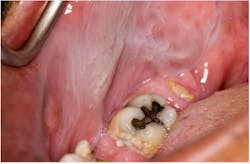

Smokeless tobacco keratosis

Smokeless tobacco can produce a thickened layer of keratin at the site of tobacco placement (figure 2). Variations in clinical appearance are due to the frequency and the amount of tobacco used.3 Common sites for smokeless tobacco keratosis are the maxillary and mandibular vestibules. Recommendations by the dental hygienist and dentist are for cessation of use, or at least altering the site of tobacco placement if the patient is unable to stop. These measures can aid in the reduction of this lesion.2